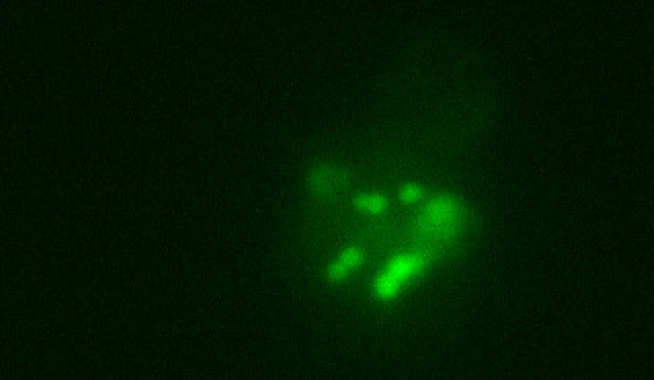

Interactions of dendritic cells and the microbiome

A major programme of work is to study the impact of different commensal/probiotic bacteria on the functioning of antigen presenting cells. Looking at the effects of different commensal bacteria on different subsets of DC is underway. Our evidence also indicates that products of commensal bacteria, as well as the bacteria themselves, have immunomodulatory function7-9. The role of the peptideSTp produced by the commensal bacterium Lactobacillusplantarum, is patented as a potential therapeutic agent for IBD. It is currently under study in preclinical trials as a treatment for mouse colitis.